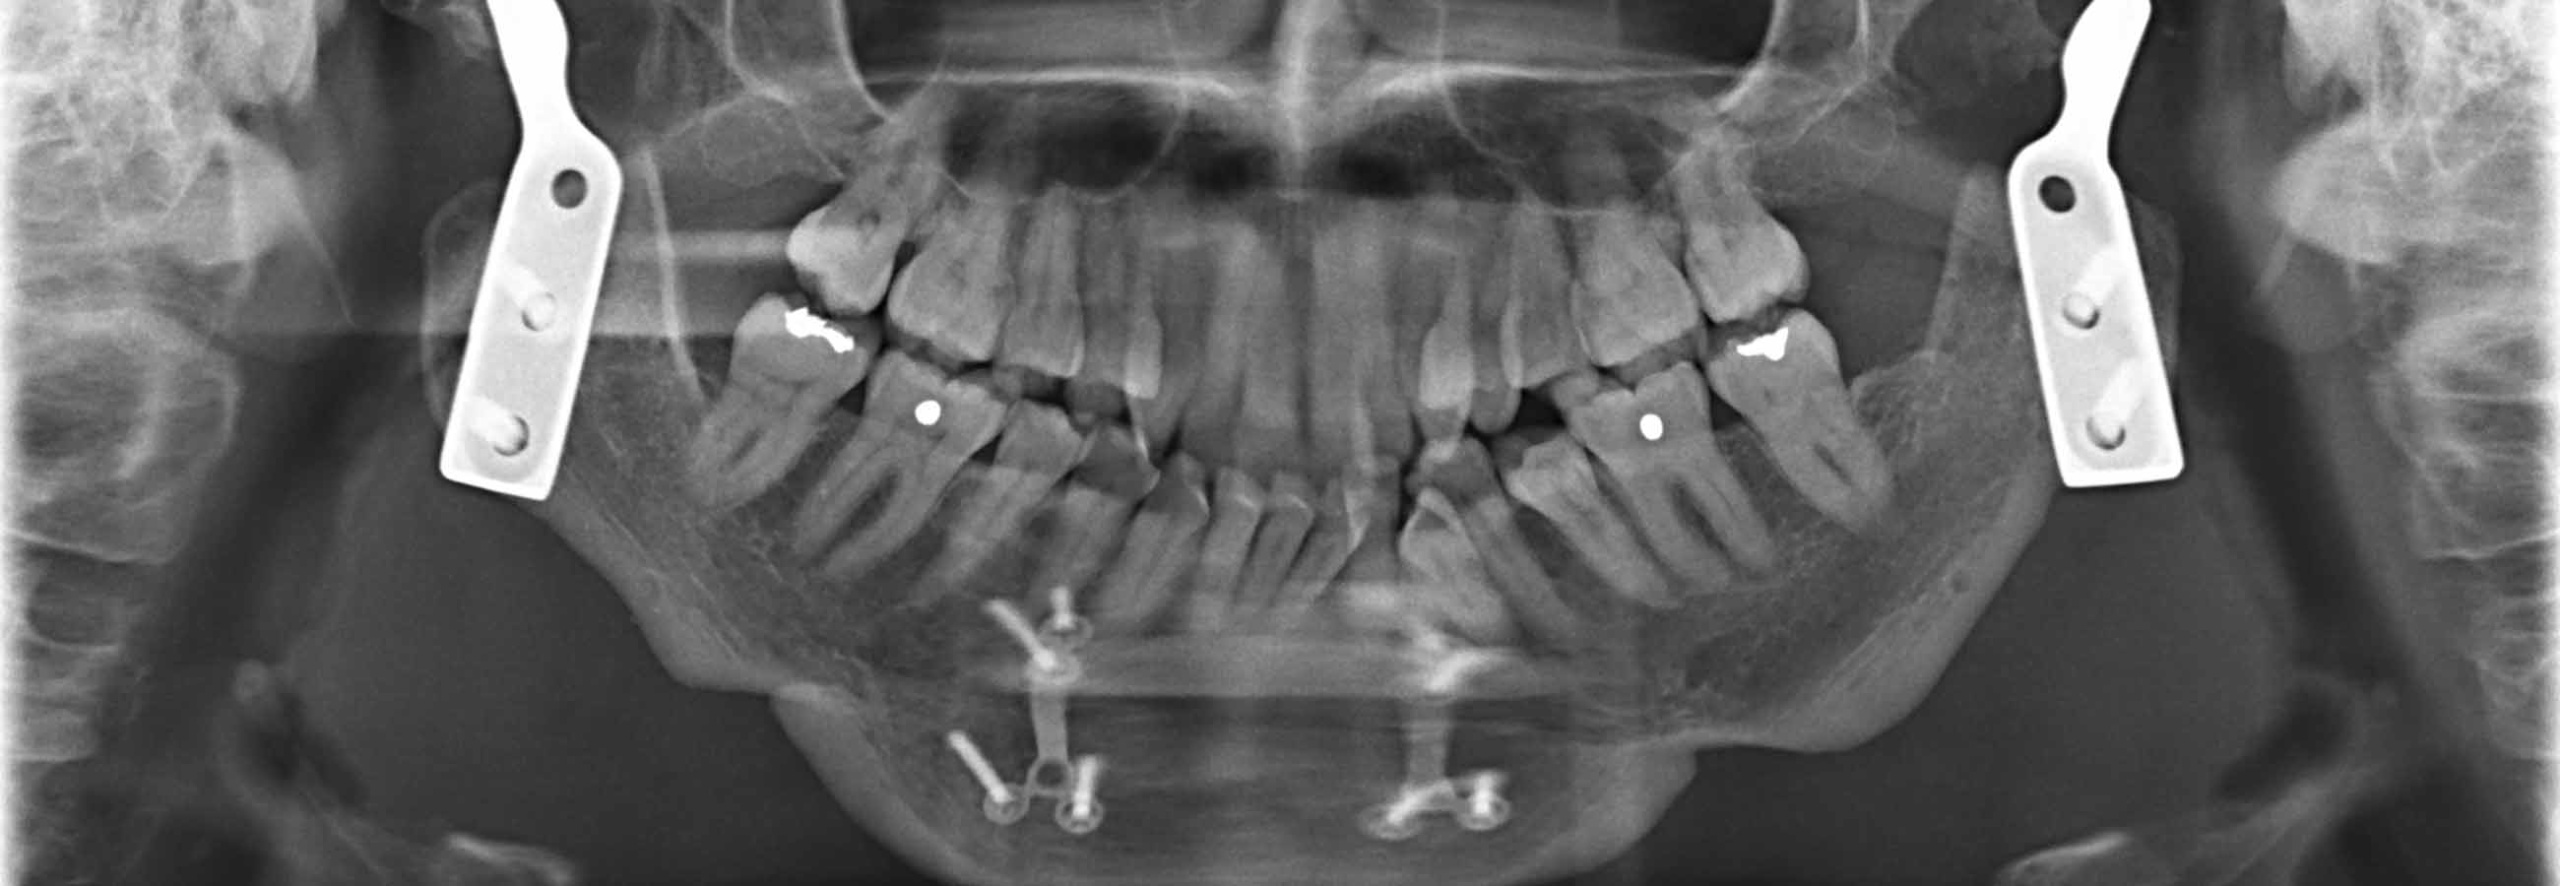

Are Dental Implants a Treatment Option for TMJ?

Are Dental Implants a Treatment Option for TMJ? Dental Implants And Tmj Tmj disorder can occur at any age, but it is most commonly reported in individuals between the ages of 20 to 40 years old. Our dedicated team of tmj specialists offers comprehensive care for temporomandibular joint disorders, addressing jaw pain, limited jaw movement, headaches, and other symptoms. At dp dental, we’ve made the tmj disorder treatment process to be as. Dental Implants And Tmj.